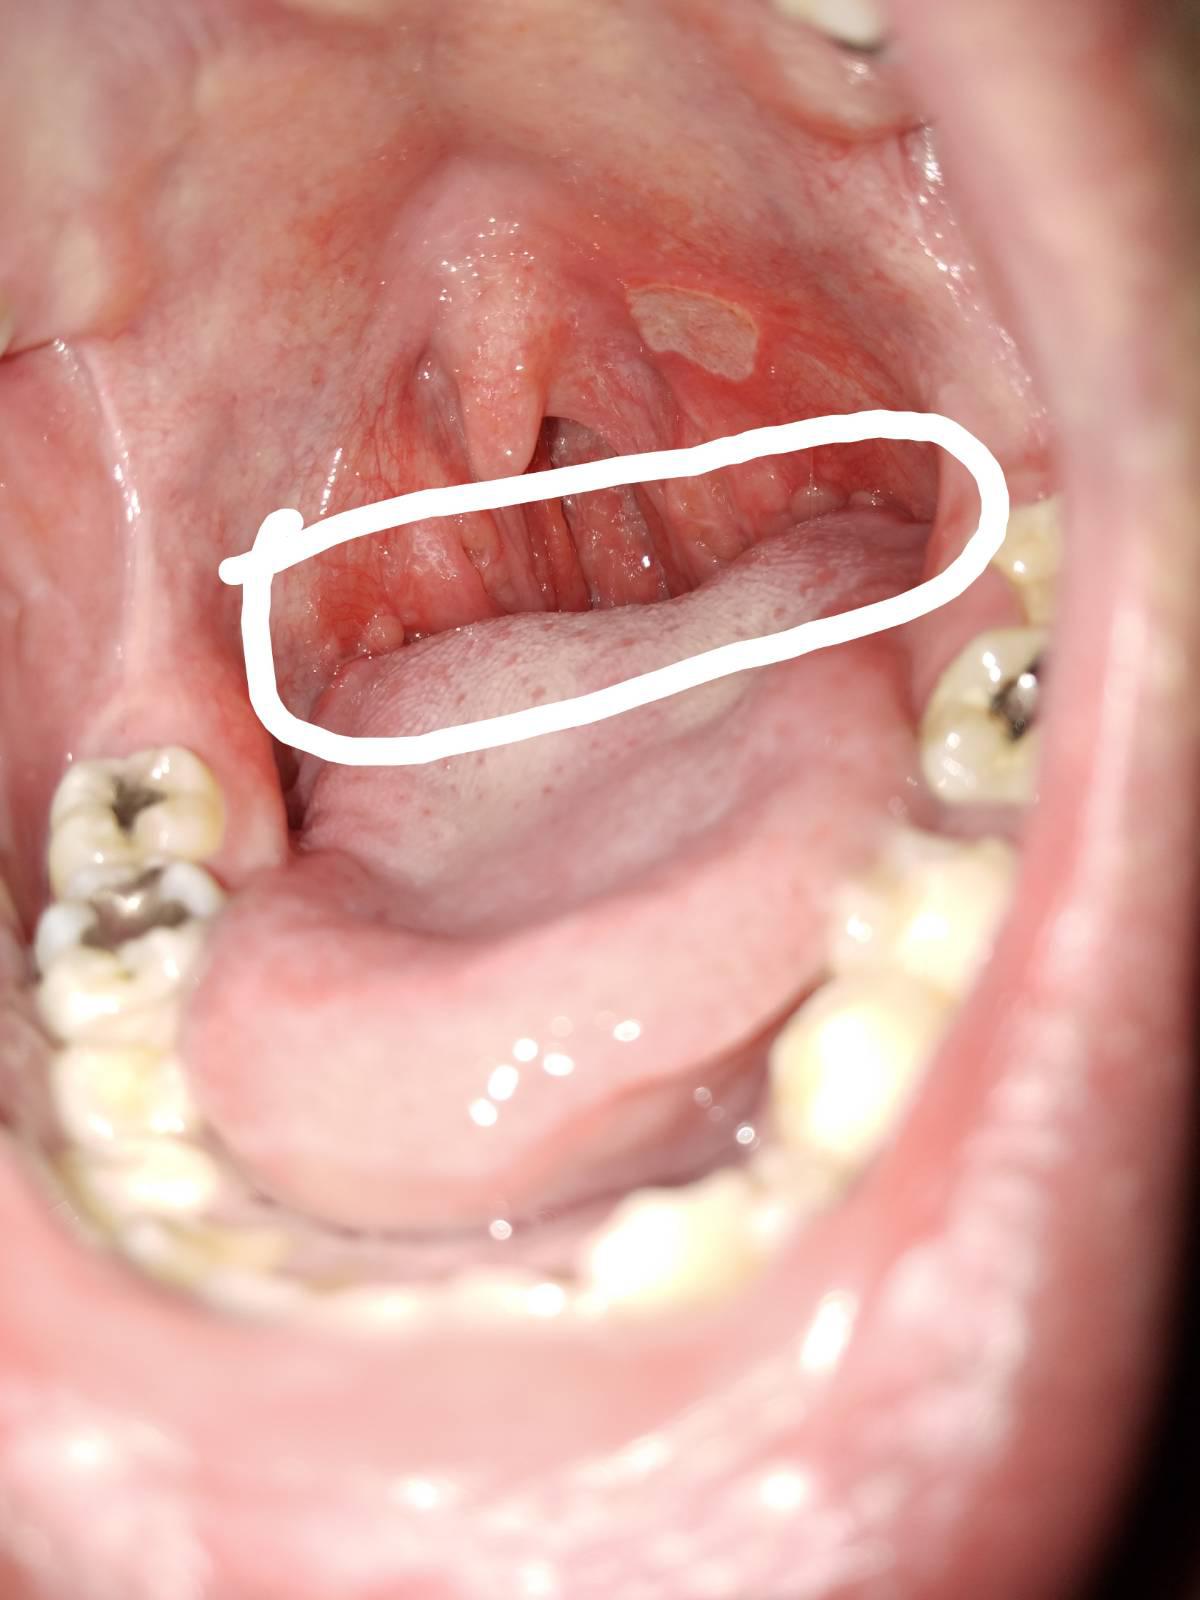

มีใครรู้บอกด้วยครับ ว่ามันเป็นอะไร??

คือเป็นมาสักเป็นปีล่ะมั้งเท่าที่สังเกต

แต่ร้อนในพึ่งเป็นได้จะอาทิตย์นึงล่ะคับ

ใครรู้ เป็นหมอมาตอบก็ได้ครับ กินยาแก้อักเสบไปครึ่งแผง แล้วครับ

เป็นมะเร็งรึป่าวครับ กังวลมาก

ขอผู้รู้มาตอบด้วยคับ ขอบคุณมากๆครับ